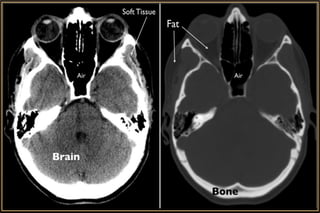

Computed Tomography

Major Considerations

• Slice thickness

• Imaging plane – Axial / Coronal / Sagittal

• Tissue window – Soft or Brain / Bone

• Contrast enhancement – Iohexol (46% Iodine)

• Better for soft tissue

• Not ideal to visualise Bony manifestations

Magnetic Resonance Imaging

• Most versatile,informative • Bony detail or calcification • Detect metallic foreign body • Inability to distinguish between pathological soft tissue masses which are radiologically isodense • Exposure to radiation - Cataract Computed Tomography

Computed Tomography Major Considerations •Slice thickness • Imaging plane – Axial / Coronal / Sagittal • Tissue window – Soft or Brain / Bone • Contrast enhancement – Iohexol (46% Iodine) • Modification of CT procedure • Orbit with Brain CT

• Better forsoft tissue • Not ideal to visualise Bony manifestations • Better resolution of Optic Nerve & Orbital Apex • No radiation • Must screen for metallic foreign bodies in orbit Magnetic Resonance Imaging